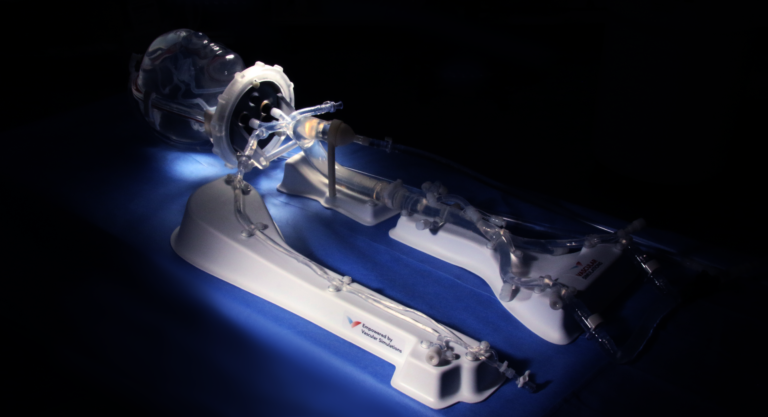

一、PRO的血管内复制系统——体验逼真的心脏驱动的逼真的生理复制

通过人血流动力学特征和逼真的触觉反馈,通过用户友好,强大且可重复的模拟来增强培训和发展。?wu限能力

复制各种血管内手术和疾病状态。

可重复且坚固

重复模拟具有真正生理功能的血管内病例。?生理和解剖学上准确的人类硅胶血管?在模拟血管内手术时,PRO?可提供的逼真的模拟体验:

三、的神经血管复制系统

复制器

的血管内复制系统

复制器的血液动力学te性可提供类似于生理流的真实心输出量,从而为设备开发和培训提供了真正的设备性能。

wu限的神经血管配置

为头或盒配置易于更换的多种神经血管疾病状态。

具有重复性的类似生活的结果

在产品演示,培训课程等中轻松且反复地模拟过程。